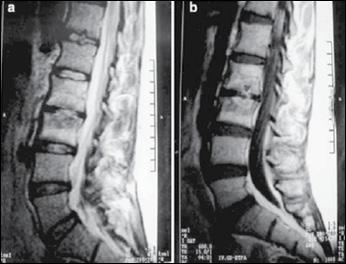

Confirman el diagnóstico pues detectan un pericardio engrosado, con frecuencia calcificado, las imágenes de elección son: la tomografía o resonancia magnética (cabe resaltar el diagnóstico diferencial con la miocardiopatía restrictiva).

Las pruebas de imagen TRATAMIENTO

La pericardiectomía (mortalidad operatoria del 7-10 %) es la única opción de tratamiento definitivo para los pacientes con pericarditis constrictiva crónica, que tienen síntomas persistentes y prominentes.